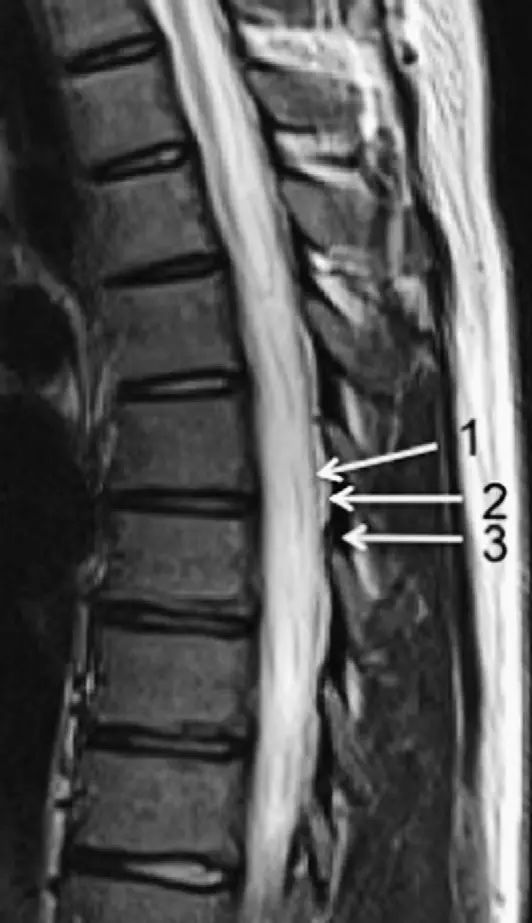

脊柱的MRI解剖

3、MRI:可显示骨折所致血肿及脊髓损伤所表现出的异常高信号。(平扫)